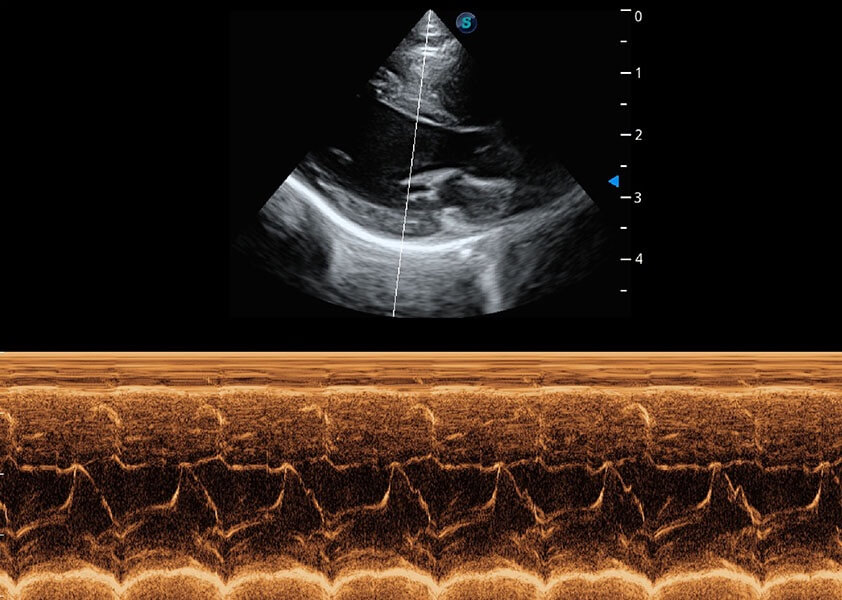

ProPet 60 作为一款高端台式动物超声设备,为动物医生的日常诊断提供了一系列贴合动物临床需求、解决临床实际问题的高级成像功能。凭借全系列高清探头,满足医生对腹部、心脏、生殖、浅表、肌骨等成像的所有需求,切实帮助您提升检查效率,提高诊断信心。

兽用彩色多普勒超声诊断系统

动物是人类最亲密的朋友和最值得信赖的伙伴。百老汇电子游戏官网也一直致力于探索动物专用的超声影像解决方案。 全新推出的ProPet系列,是百老汇电子游戏官网在动物超声影像智能化、专业化、精准化的一次跨越式革新。动物不能用言语来表述自己的不适,通过超声影像,ProPet系列搭建了动物医生与不同物种沟通的“桥梁”,为动物医生注入了“治愈之力”。